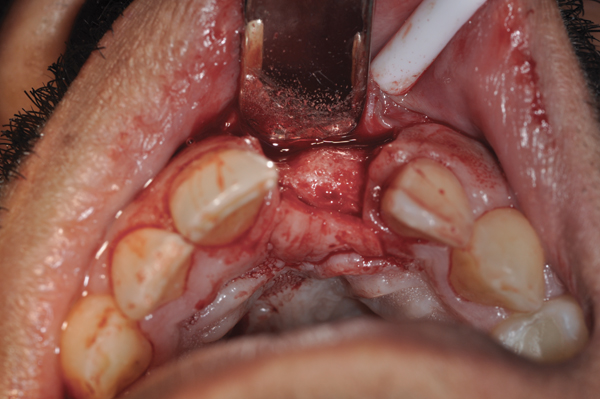

The four presented cases shown in Figure 1 through Figure 25 were all treated in a similar manner as outlined in detail in the captions for the first case (Figure 1 through Figure 11). In all four cases, teeth with pathosis were removed, buccal and lingual flaps were elevated, and sites were surgically debrided. A Cytoplast d-PTFE barrier was sized and inserted usually under the buccal flap, the bone graft was added, the barrier was then tucked under the lingual flap, and the flaps were sutured. Bone grafts were used in all of the cases, because buccal bony plates were resorbed and the bone graft helped support the barrier.

Fig 1. (Case 1) Tooth No. 19 manifested a buccal fistulous tract. Probing depth on the buccal was 8 mm.

Figure 1

Fig 2. Buccal flap elevated exposing buccal plate defect.

Figure 2